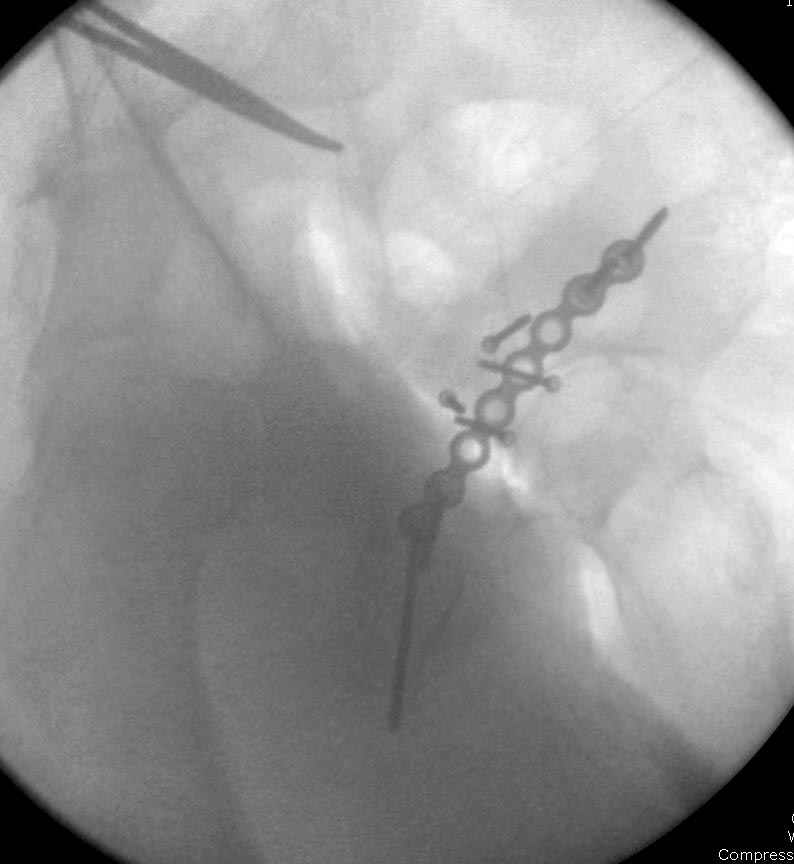

7:30 начало операции, больной на спине, попытка репозиции после анестезии N3, укладка больного на боку, доступ Kocher- Langenbeck, состояние седалищнего нерва около 2.5см кровоподтек, через joistick головка бедра приподнята, освобовождение сустава, фрагмент заднего края более 3х4 см репонирован на свое место. После промывания

сустава, репозиция вывиха (N4), фиксация фрагмента 2.7(4) мм шурупами и допольнительно реконструктивной пластиной на 8 дырок, фиксация 3.5мм шурупами проксимально и дистально.

Интраоперционные N5 косая запирательная и N6 подвздошный снимок